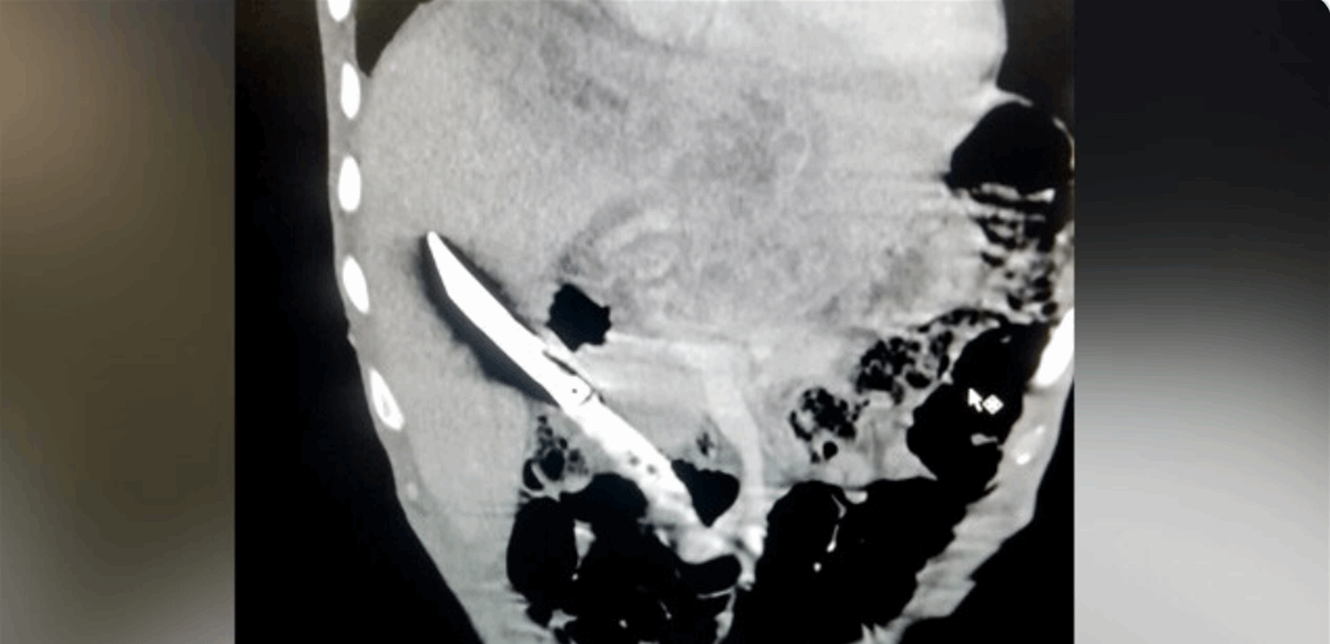

Ножевое В Живот Фото